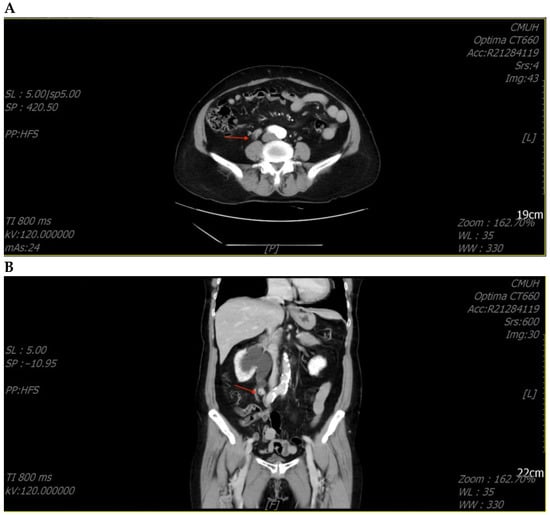

A 71-year-old female patient with a history of recurrent stone disease presented with abdominal pain. She denied a history of diabetes and hypertension. She had been treated for bilateral urolithiasis for 12 years, including a left kidney stone that had been treated with extracorporeal shock wave lithotripsy (ESWL), a right ureteral stone that had been treated with ureterorenoscopic surgery, and a right renal stone that had been treated with ESWL. She presented with symptoms of painless gross hematuria and abdominal pain in May 2022. The renal echo revealed right hydronephrosis and a small renal stone. Intravenous pyelography showed a small upper ureteral stone with obstruction at the right upper ureter (Figure 1).

Figure 1. Intravenous pyelography revealed an obstruction at the right upper ureter (arrowhead).